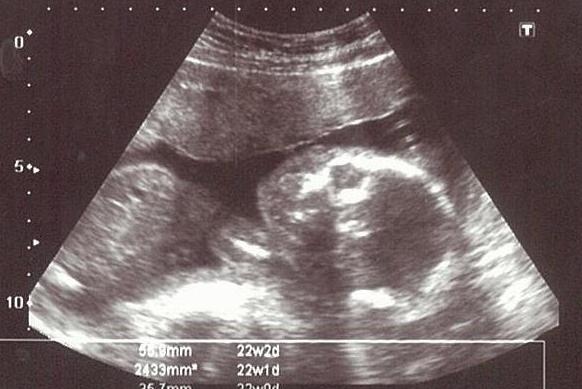

17~20週 第三次產檢 羊膜穿刺+晶片、高層次超音波

事先順利在網路上掛號,當天下午按照指示時間前往柯滄銘婦產科。不到13:00就已經有人在診所裡等著抽號碼牌(當天是12:55開放抽號碼),不過因為上午人太多,有幾位孕媽咪被延後到下午才抽羊水(真的很辛苦啊~)。所以,雖然按照時間抵達,還是等待了約一個小時。首先要先到櫃檯拿初診單填寫,然後按照燈號到櫃檯填寫同意書、報告收件信封袋、繳錢(羊膜穿刺3,000+晶片18,000),之後就是等待到診間診間的燈號。進入診間會有專人確認且說明今天要檢查的項目,接著進去照超音波看寶寶的週數、狀況與羊水量,再來就是等柯醫師來執行啦~